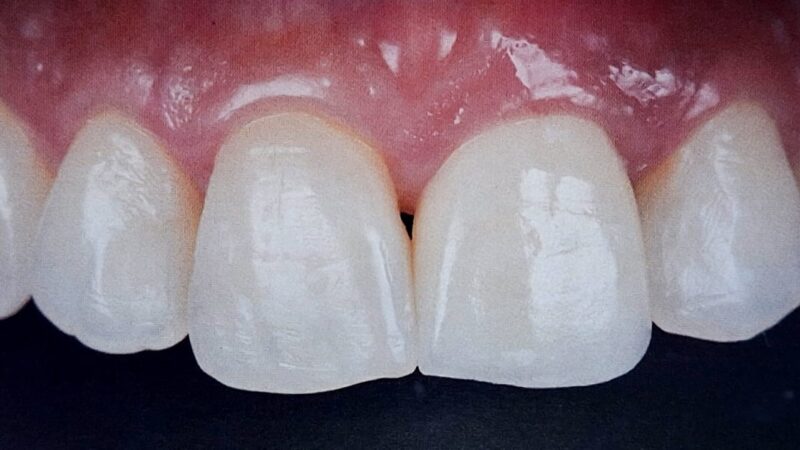

Veja aqui como são os novos critérios quantitativos que mudam a percepção da estética na prótese unitária sobre implantes.